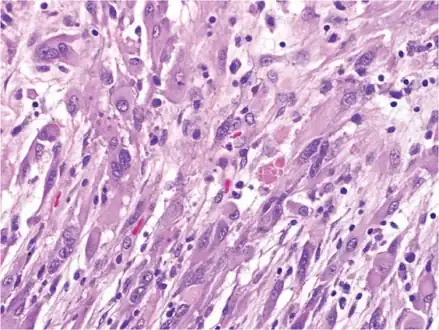

An image of a brain with pleomorphic xanthoastrocytoma